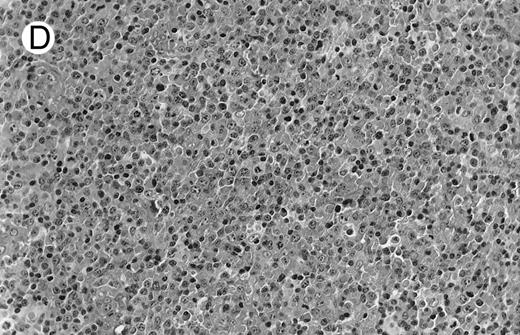

Diffuse large B-cell lymphomas (REAL classification)9 or centroblastic lymphoma (Kiel classification)8 were observed in the last 4 cases, 1 nodal (case no. 9) and 3 extranodal, involving stomach, skin, and parotid (cases no. 2, 7, and 16). The gastric (case no. 2) and the skin (case no. 7) lymphomas were considered as a blastic transformation of a low-grade MALT-type lymphoma because large tumoral cells were mixed with a monoclonal plasmacytic cell component (Fig 1F ). The pathological features of these high-grade lymphomas did not differ from conventional centroblastic lymphoma. A high-grade diffuse large B-cell lymphoma was also subsequently diagnosed in the retroperitoneal area 10 months after the initial bronchial low-grade MALT type lymphoma in 1 patient (case no. 5). Lastly, 1 patient (case no. 13) with a gastric low-grade MALT-type lymphoma subsequently developed a nonepidermotropic cutaneous CD4 T-cell lymphoma.

(D) Case no. 10. Immunocytoma in lymph node. The infiltrate is composed of small lymphocytes, plasma cells and blasts. (E) Case no. 14. Monocytoid B-cell lymphoma in a cervical lymph node with a monocytoid component located in dilated sinuses.

(F ) Case no. 2. High-grade B-cell lymphoma in the stomach (centroblastic lymphoma; upper), with remnants of low-grade lymphoma of MALT type (lower).